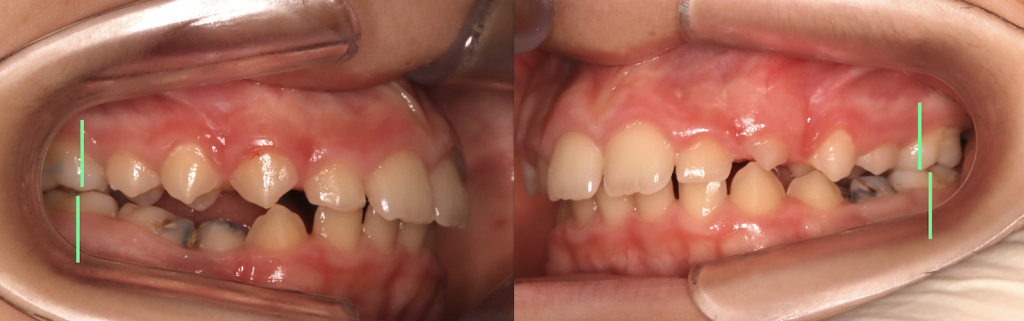

Consegniamo l’apparecchio ortodontico miofunzionale con indicazione di portarlo qualche ora durante il giorno per le prime due settimane (per abituarsi a tenerlo senza perderlo tutta la notta) e tutta la notte. Ecco i risultati dopo 3 mesi di apparecchio.

Due cose mi piaccionon molto di questo caso:

1. I molari e la classe sono quasi perfetti

2. Il piano masticatorio è piatto

Prima di iniziare il trattamento i denti posteriori si incurvavano in una maniera poco armonica e funzionale. Dopo soltanto tre mesi di apparecchio, è migliorata la funzione masticatoria, deglutitoria e respiratoria. Ma l’effetto che si vede è un miglioramento della posizione della dentatura e delle ossa.

Non posso che essere orgoglioso di un caso del genere! Sono riuscito a migliorare il pattern di crescita della mandibola, che è una delle situazioni più difficili da migliorare. E questo è stato fatto non lavorando meccanicamente sullo spostamento dentale, ma passivamente solo attraverso il cambio di funzione orale.

Adesso devo solamente aspettare che cadano i denti da latte, nel frattempo il paziente continuerà a portare l’apparecchio per garantire il mantenimento della posizione ossea e guidare la corretta eruzione dei denti permanenti.